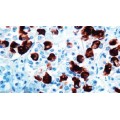

Positive Control: Pituitary

Cellular Localization: Cytoplasmic

Specificity: This antibody reacts with human ACTH. This antibody cross-reacts with

ACTH in a wide variety of mammalian species. Traces of contaminating antibodies have

been removed by solid phase adsorption.